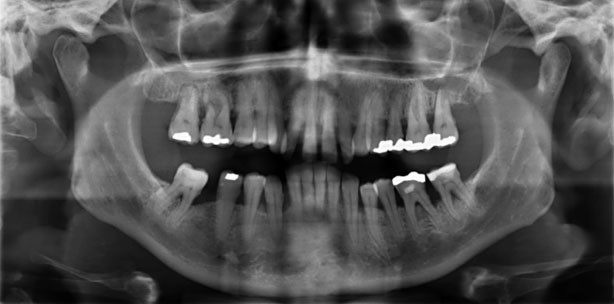

Abb. 2: Vor der Therapie: deutliche livide Verfärbung und Schwellung der Gingiva (ST bis 8 mm mit BoP).

Abb. 3: Nach der Therapie: blande Verhältnisse, ST bis 4 mm, kein BoP, deutliche Rezessionen (v.a. UK).